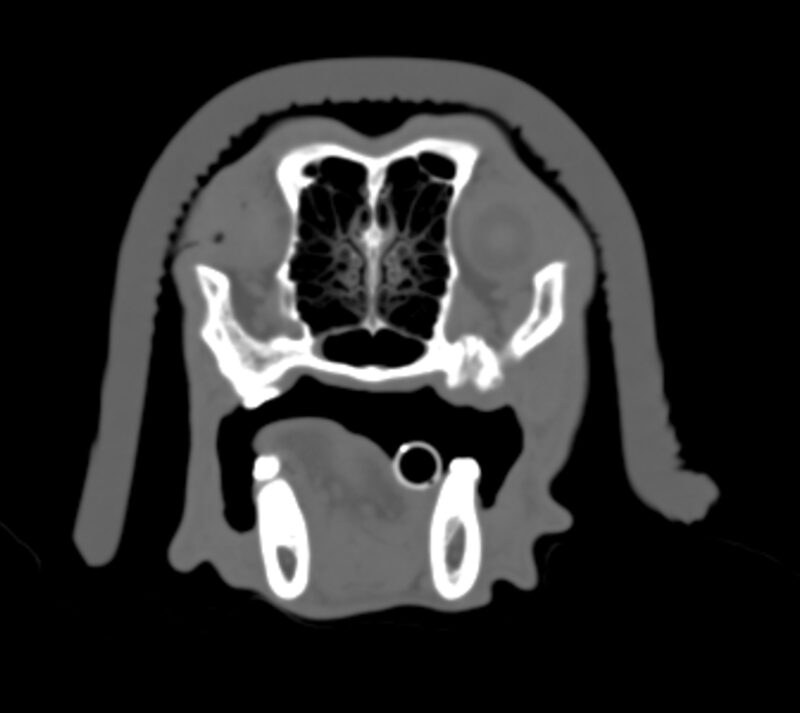

Die Strahlentherapie sowie die jeweils notwendigen Narkosen sind gut verträglich und sicher, sodass Komplikationen extrem selten sind. Im Verlauf der Strahlentherapie ist aber mit Reaktionen zu rechnen, die bereits im Vorfeld aufgeklärt und besprochen werden müssen. Grundsätzlich sind frühe von späten Strahlenreaktionen zu unterscheiden. Frühe Strahlenreaktionen sind bei definitiven Protokollen ausgeprägter als bei palliativen, treten ca. 14 Tage nach Therapiebeginn auf, heilen aber auch bis ca. 21 Tage nach Therapieende vollständig ab. Der vorliegende Fall zeigt eine Vielzahl von zu erwartenden Strahlenreaktionen sehr eindrücklich. In Abbildung 1 ist ein Schnitt des CT zur Strahlentherapieplanung auf Höhe M1 dargestellt. Neben dem Tumorvolumen ist auch das Planungsvolumen (späterer Hochdosisbereich) sowie die Risikoorgane Auge und Zunge konturiert. Aus dieser Abbildung sind die zu erwartenden Nebenwirkungen gut abzuschätzen, da folgende Strukturen im Hochdosisbereich liegen: Maulschleimhaut, Teile der Nasenhöhle, kutane Haut. Außerdem reicht das Planungsvolumen bis an das Auge heran, sodass auch dieses einem Risiko ausgesetzt ist.